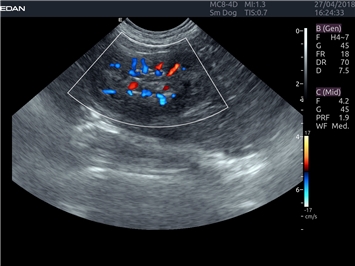

EDAN Acclarix LX4 VET

EDAN Acclarix LX4 VET представляет собой профессиональную ультразвуковую систему, специально разработанную для ветеринарных исследований. Сочетание стабильности, высокой производительности и эффективности делает эту систему идеальным выбором для современной ветеринарной практики.

Энергетический допплер:

Цветовой допплер: